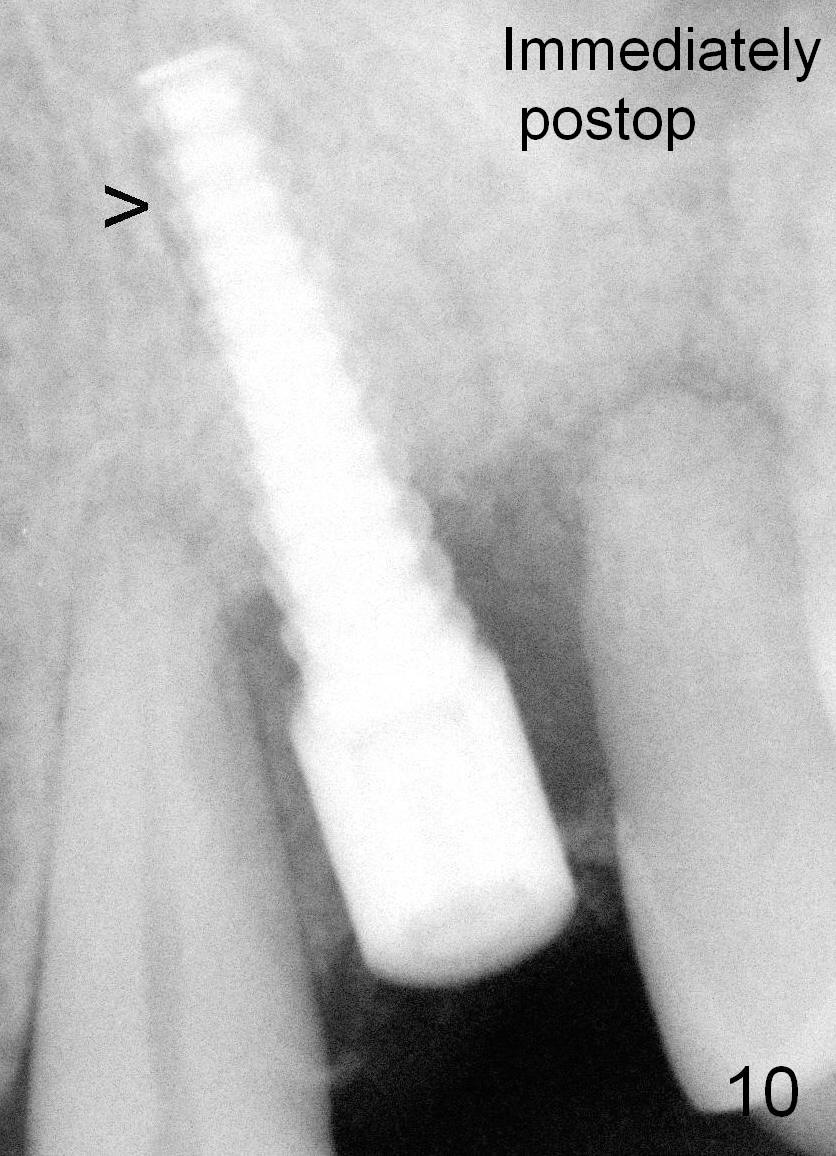

Fig.3,7,10-14 (at the same magnification) show regrowth of crestal bone around the implant postop.

Fig.10: Arrowhead: space due to change of osteotomy.